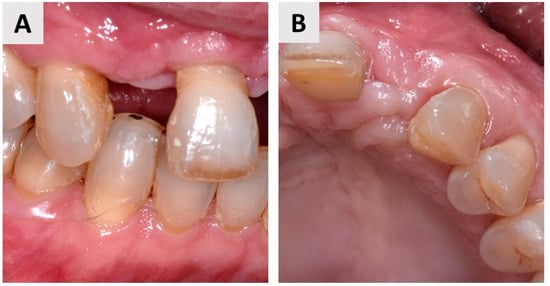

4. Case Report Two: GBR with Immediate Implant Placement